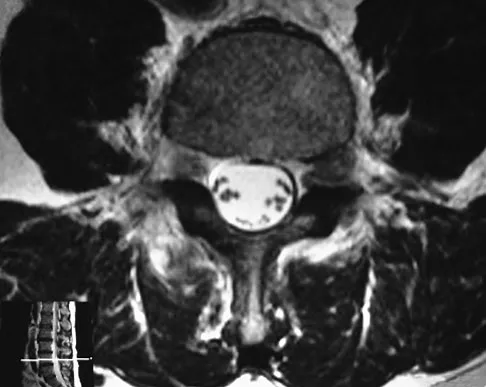

Question 58 High Yield

Figure 33 shows the MRI scan of a 55-year-old woman who has had a 6-week history of back and leg pain. Which of the following clinical scenarios is most consistent with the MRI scan findings at L4-L5?

Detailed Explanation

The MRI scan reveals a L4-L5 foraminal disk herniation originating from the L4-5 disk space that has migrated up into the foramen, compressing the left L4 nerve root. There is normal distribution of the roots in the cerebrospinal fluid, excluding arachnoiditis as a diagnosis, and disk herniation in this location would not result in cauda equina syndrome or myelopathy.